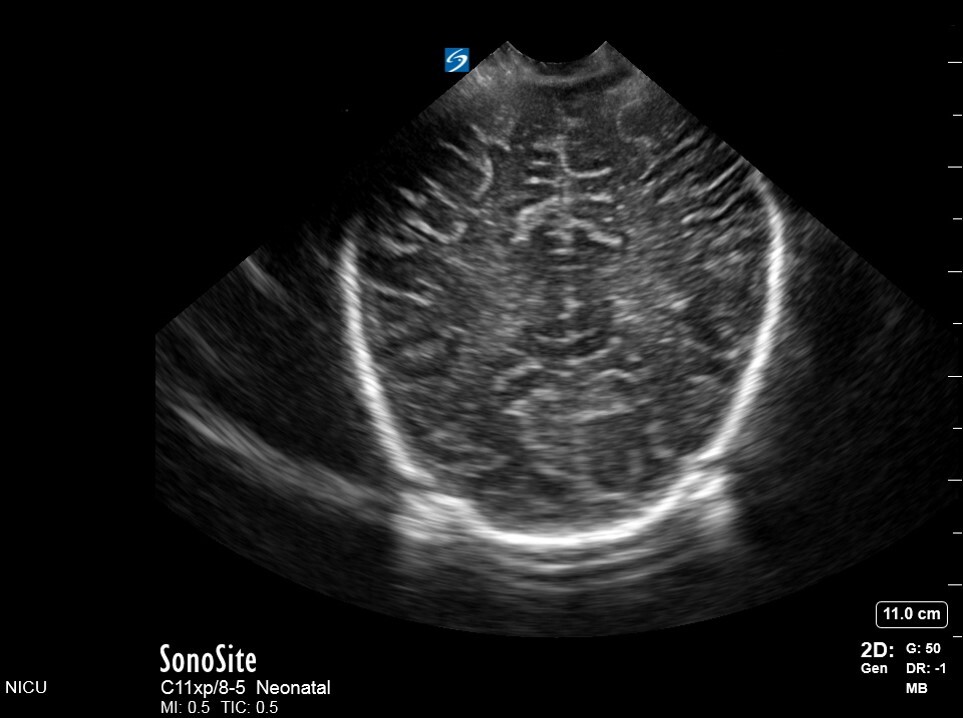

Neonatology C6 1 Image